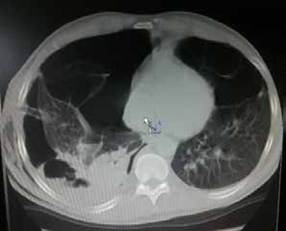

En el leucograma del momento del derrame pleural se encontró: leucocitosis con predominio de los polimorfonucleares (leucocitos: 12,6 x 109/L; polimorfonucleares: 85,9 %). Se decidió practicar una pleurotomía mínima baja, añadiendo otro antibiótico y manteniendo la terapia respiratoria, medidas que contribuyeron a la mejoría de la sintomatología. Posteriormente, al pinzar los drenajes torácicos, el pulmón se colapsó nuevamente, por lo que se le hizo una tomografía computarizada (TC). Se observó escaso parénquima pulmonar con múltiples bullas de diferente tamaño diseminadas en ambos campos pulmones, algunas de ellas con niveles hidroaéreos en su interior en la base del hemitórax derecho; también, había moderado colapso pulmonar derecho (figura 2).